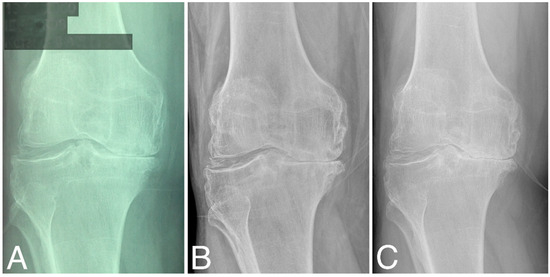

Structural changes in the distal femur and proximal tibia are evaluated according to KL classification (Table 1). At baseline, three patients were classified as grade 2, four as grade 3, and four as grade 4. At 60 months, KL scores did not change significantly (two as grade 2, three as grade 3, and five as grade 4), (Wilcoxon signed-rank test, Z = −1.095445, p = 0.273322). At 80 months, KL grades decreased significantly compared to that at baseline (three as grade 3 and seven as grade 4), (Wilcoxon signed-rank test, Z = −2.201398, p = 0.027708). Representative radiographies are given in Figure 3.

Figure 3.

X-ray images of the right knee (A) at baseline, (B) at 60 months time point, and (C) at 84 months time point; all are classified as KL grade 4.